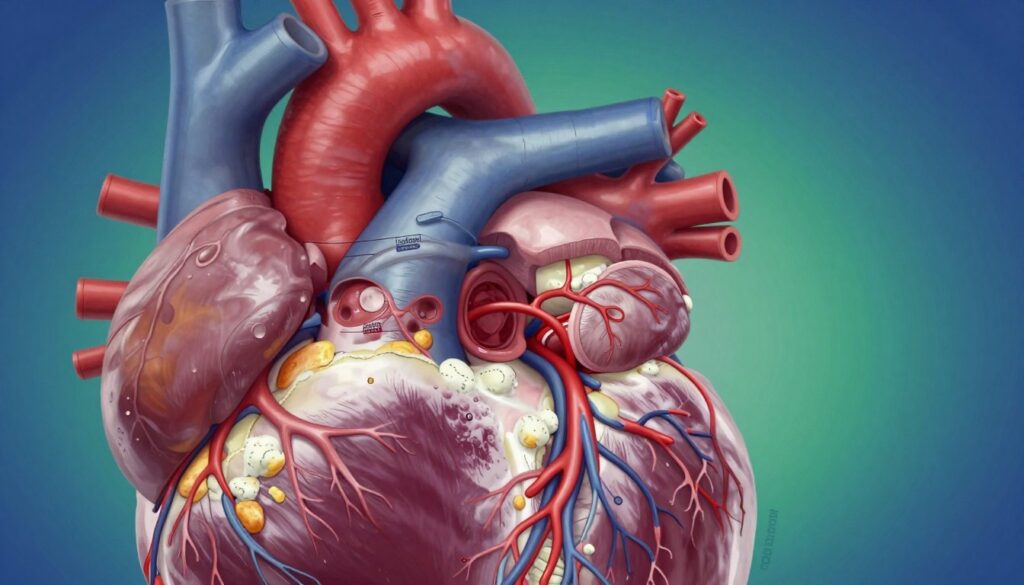

Did you know your body makes cholesterol to build healthy cells? While it’s vital, too much LDL cholesterol can be harmful. It can block arteries, limiting blood flow to your heart and other organs.

Keeping your heart healthy is more than just avoiding bad habits. It’s about taking a proactive approach to your daily life. Knowing how your circulatory system works helps you make simple changes to protect your health.

Heart disease often starts with small changes in your arteries. You might feel fine, but tiny processes are happening inside you. Knowing about these changes is key to keeping your heart healthy.

What is Atherosclerosis?

Atherosclerosis means your arteries get clogged with fatty stuff. It starts when cholesterol particles stick to your artery walls. Your body sees this as a threat and sends white blood cells to fight it.

This fight creates inflammation. Over time, cholesterol and immune cells build up, forming plaque. This buildup can block blood flow to your organs.

Managing Blood Pressure and Cholesterol Levels

Keeping your heart healthy means watching your blood pressure and cholesterol closely. Keeping these levels in check helps your heart work better. It’s key to stop artery narrowing before it’s too late.

Monitoring Your Numbers Regularly

Your blood pressure and cholesterol are like a map for your heart. High blood pressure makes your heart work too hard. This can damage your blood vessels and lead to artery narrowing.

Knowing your lipid levels is also crucial. A high HDL level means less risk of heart disease. Your LDL goal depends on your health risk, so talk to your doctor about it.